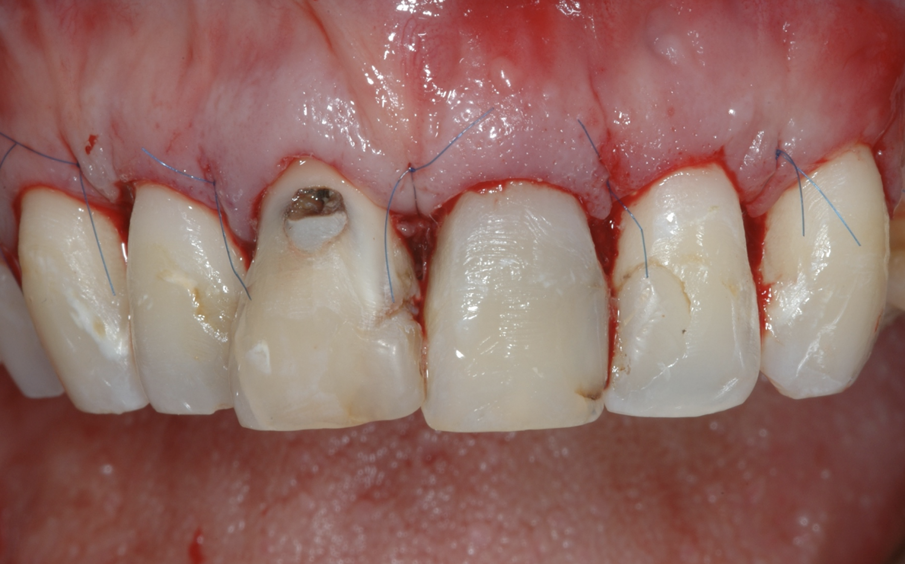

Fig. 7 - La sutura al termine dell’intervento.